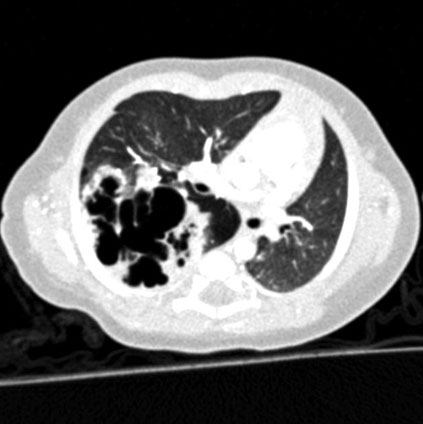

CT scan showing congenital cystic adenomatoid malformation (CCAM) with multiple cystic lesions in the fetal lung